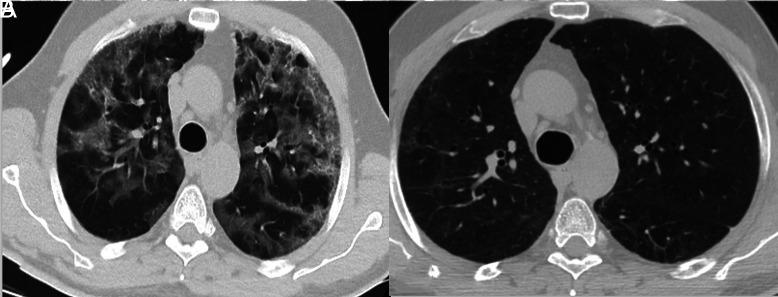

Results: The mean age was 64.4 ± 13.5 years, and 44 (62.9%) of them were male. The most frequently encountered comorbidities were cardiovascular disease (57.1%) and lung disease (22.9%). While PaO2 levels increased in both groups during the follow-up period, this increment was significantly higher in group I (PaO2: 66.6 ± 9.9 mm Hg, P < .001). The factors affecting the LTOT requirement were evaluated using binary logistic regression. On multivariate analyses of lymphocytes, ferritin, C-reactive protein, PaO2, SaO2, subpleural reticulation, and number of lobes affected (≥3 lobes), the SaO2 level and presence of subpleural reticulation were significantly different between the 2 groups [odds ratio (OR) (95% CI): 0.853 (0.749-0.971), P = .016] and [OR (95% CI): 0.171 (0.042-0.733), P = .017], respectively.

Conclusion: A significant proportion of patients who develop respiratory failure due to COVID-19 recover within the first 3 months. Factors determining the LTOT requirement for more than 3 months were SaO2 and the presence of subpleural reticulation.